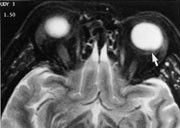

I de tilfeller der ultralydundersøkelse ikke med full sikkerhet kan differensiere mellom primær retinal affeksjon (som Coats sykdom, primær persisterende hyperplastisk corpus vitreum, massiv retinal gliose eller premature endringer assosiert med subretinal væske eller blødning) og sekundære retinale forandringer med mulig underliggende vev, anbefales MR (fig 1). Solide svulster som er større enn 2 mm i tykkelse (retinoblastom, leiomyom, koroidalt melanom og retinalt kapillært hemangiom) er høysignalgivende på T1 og har lavt signal på T2-vekting (fig 2). Ved å vurdere T1-serien kan man skille mellom en enkel effusjon og en mer alvorlig sykdom (4).

En vanlig effusjon er hypo-/isointens, dog kan effusjoner gi litt høyere signal på T1-vekting grunnet høyt proteininnhold. Blødning gir høyt signal. Solid tumor har vanligvis lavere signal på T2-bilder enn væske.